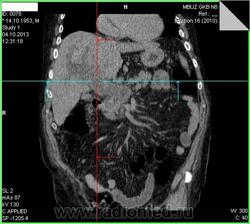

- https://radiomed.ru/sites/default/files/styles/case_slider_image/public/user/15361/00bd452f.jpg?itok=7Yqpn566

- https://radiomed.ru/sites/default/files/styles/case_slider_image/public/user/15361/00bfee95.jpg?itok=PUcrVzyc

- https://radiomed.ru/sites/default/files/styles/case_slider_image/public/user/15361/00c0937f.jpg?itok=7U4D1tv_

- https://radiomed.ru/sites/default/files/styles/case_slider_image/public/user/15361/00ca7eed.jpg?itok=rr_xi6tP

- https://radiomed.ru/sites/default/files/styles/case_slider_image/public/user/15361/00cb6df1.jpg?itok=1nPv330F

- https://radiomed.ru/sites/default/files/styles/case_slider_image/public/user/15361/00cb352d.jpg?itok=EVSnuZCO

- https://radiomed.ru/sites/default/files/styles/case_slider_image/public/user/15361/00cce936.jpg?itok=PqpE7v3O

- https://radiomed.ru/sites/default/files/styles/case_slider_image/public/user/15361/00cd0fba.jpg?itok=XHp74aU2

- https://radiomed.ru/sites/default/files/styles/case_slider_image/public/user/15361/00cd29f9.jpg?itok=H17OxJCX

Контраст тоже не завезли? Блок БДС возможен.

Тоже вижу расширенные желчные протоки. Освойте экспорт изображений в формате дайком, тогда сможете размещать из на сайте, советы будут более предметными.

+1. Дайте дайкомы посмотреть. Возможна обструкция интрапанкреатической части холедоха или еще ниже. А для итерпретации очагов в печени желательно контрастное усиление сделать.

При патологии печени очень желательно указывать наличие/отсутствие болевого синдрома, желтухи. Большинство КТ-исследований гепато-панкреато-дуоденальной зоны (а эта зона является одной из самых трудно трактуемых в брюшной полости) без контраста является мало информативным способом облучения пациента . Фокусные изменения и расширение внутрипеченочных желчных протоков было видно и на УЗИ. Понятно, что не всегда есть контраст, но ... в-общем, попробуем выжать максимум из имеющегося, если у Вас получится закинуть архив дайкома на файлообменник.

. Фокусные изменения и расширение внутрипеченочных желчных протоков было видно и на УЗИ. Понятно, что не всегда есть контраст, но ... в-общем, попробуем выжать максимум из имеющегося, если у Вас получится закинуть архив дайкома на файлообменник.